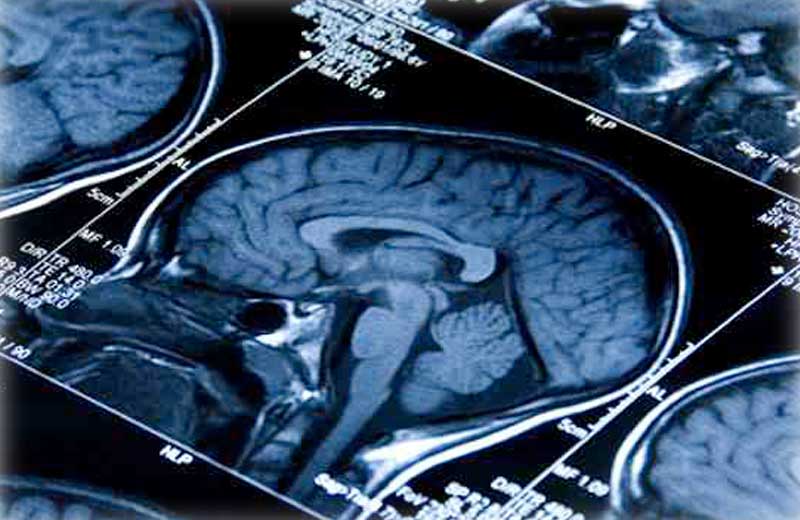

Uma nova combinação de medicamentos funcionou bem contra o câncer no cérebro de Lisa Rosendahl, de 26 anos.

Depois que o câncer se tornou resistente à quimioterapia e, em seguida, para tratamentos direcionados, os médicos deram a ela apenas alguns meses vida.

Mas agora, a combinação de remédios estabilizou a doença de Lisa Rosendahl e aumentou a quantidade e a qualidade de vida da jovem.

Ao adicionar a droga cloroquina anti-malária ao tratamento, a combinação parou o processo que as células de câncer usavam para resistir à terapia.